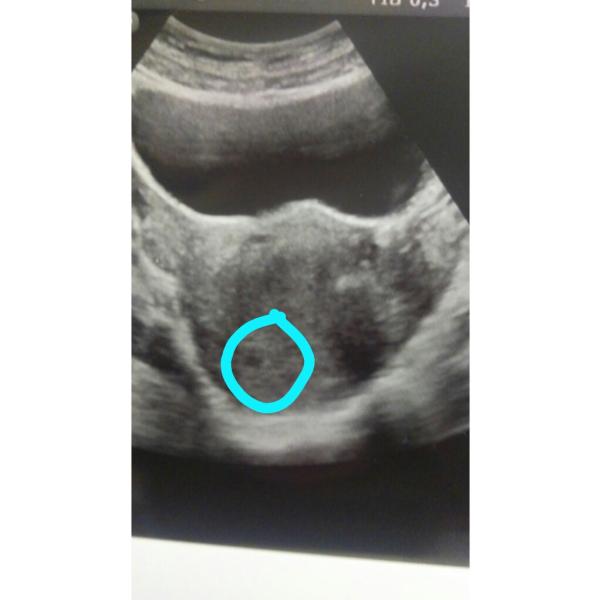

Поздравляю😍😍😍😍💖💖💖я тоже радовалась что в первую что во вторую беременность,в первую в 5 недель пошла на УЗИ))а во второй тоже в 4-5 недель))а потом уже пошла сердцебиение посоушать в 6 недель 😍а сейчас нам уже 14-15 недель😍😍😍саг саламат😍💖💋